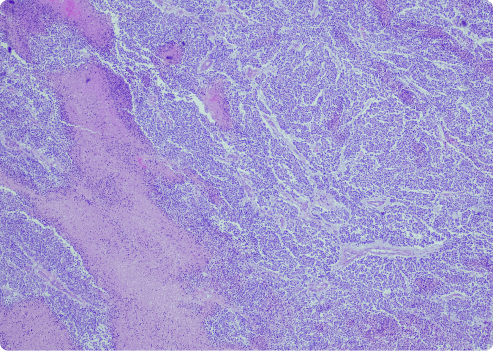

Desmoplastic mesothelioma is a unique type of sarcomatoid mesothelioma. The term “sarcomatoid” describes long, spindle-shaped cells. This subtype is rare. It can be more aggressive than other forms of mesothelioma.

This variant has dense fibrous tissue and fewer cells. Desmoplastic cells are hard to identify. They lack clear patterns. These types of mesothelioma cells form dense nodules of connective tissue in tumors. This can make diagnosis more difficult.